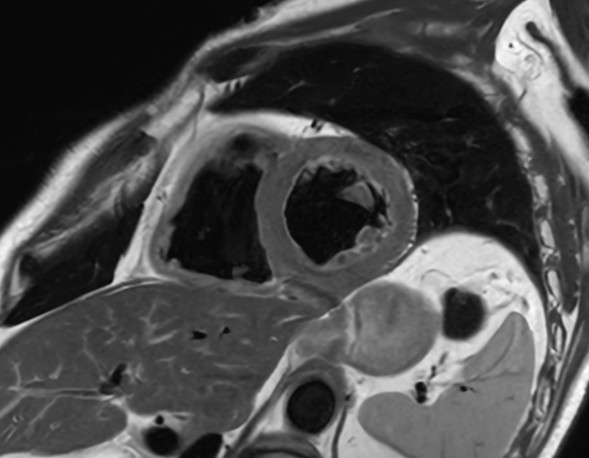

Comprehensive Cardiac with SmartSpeed Precise